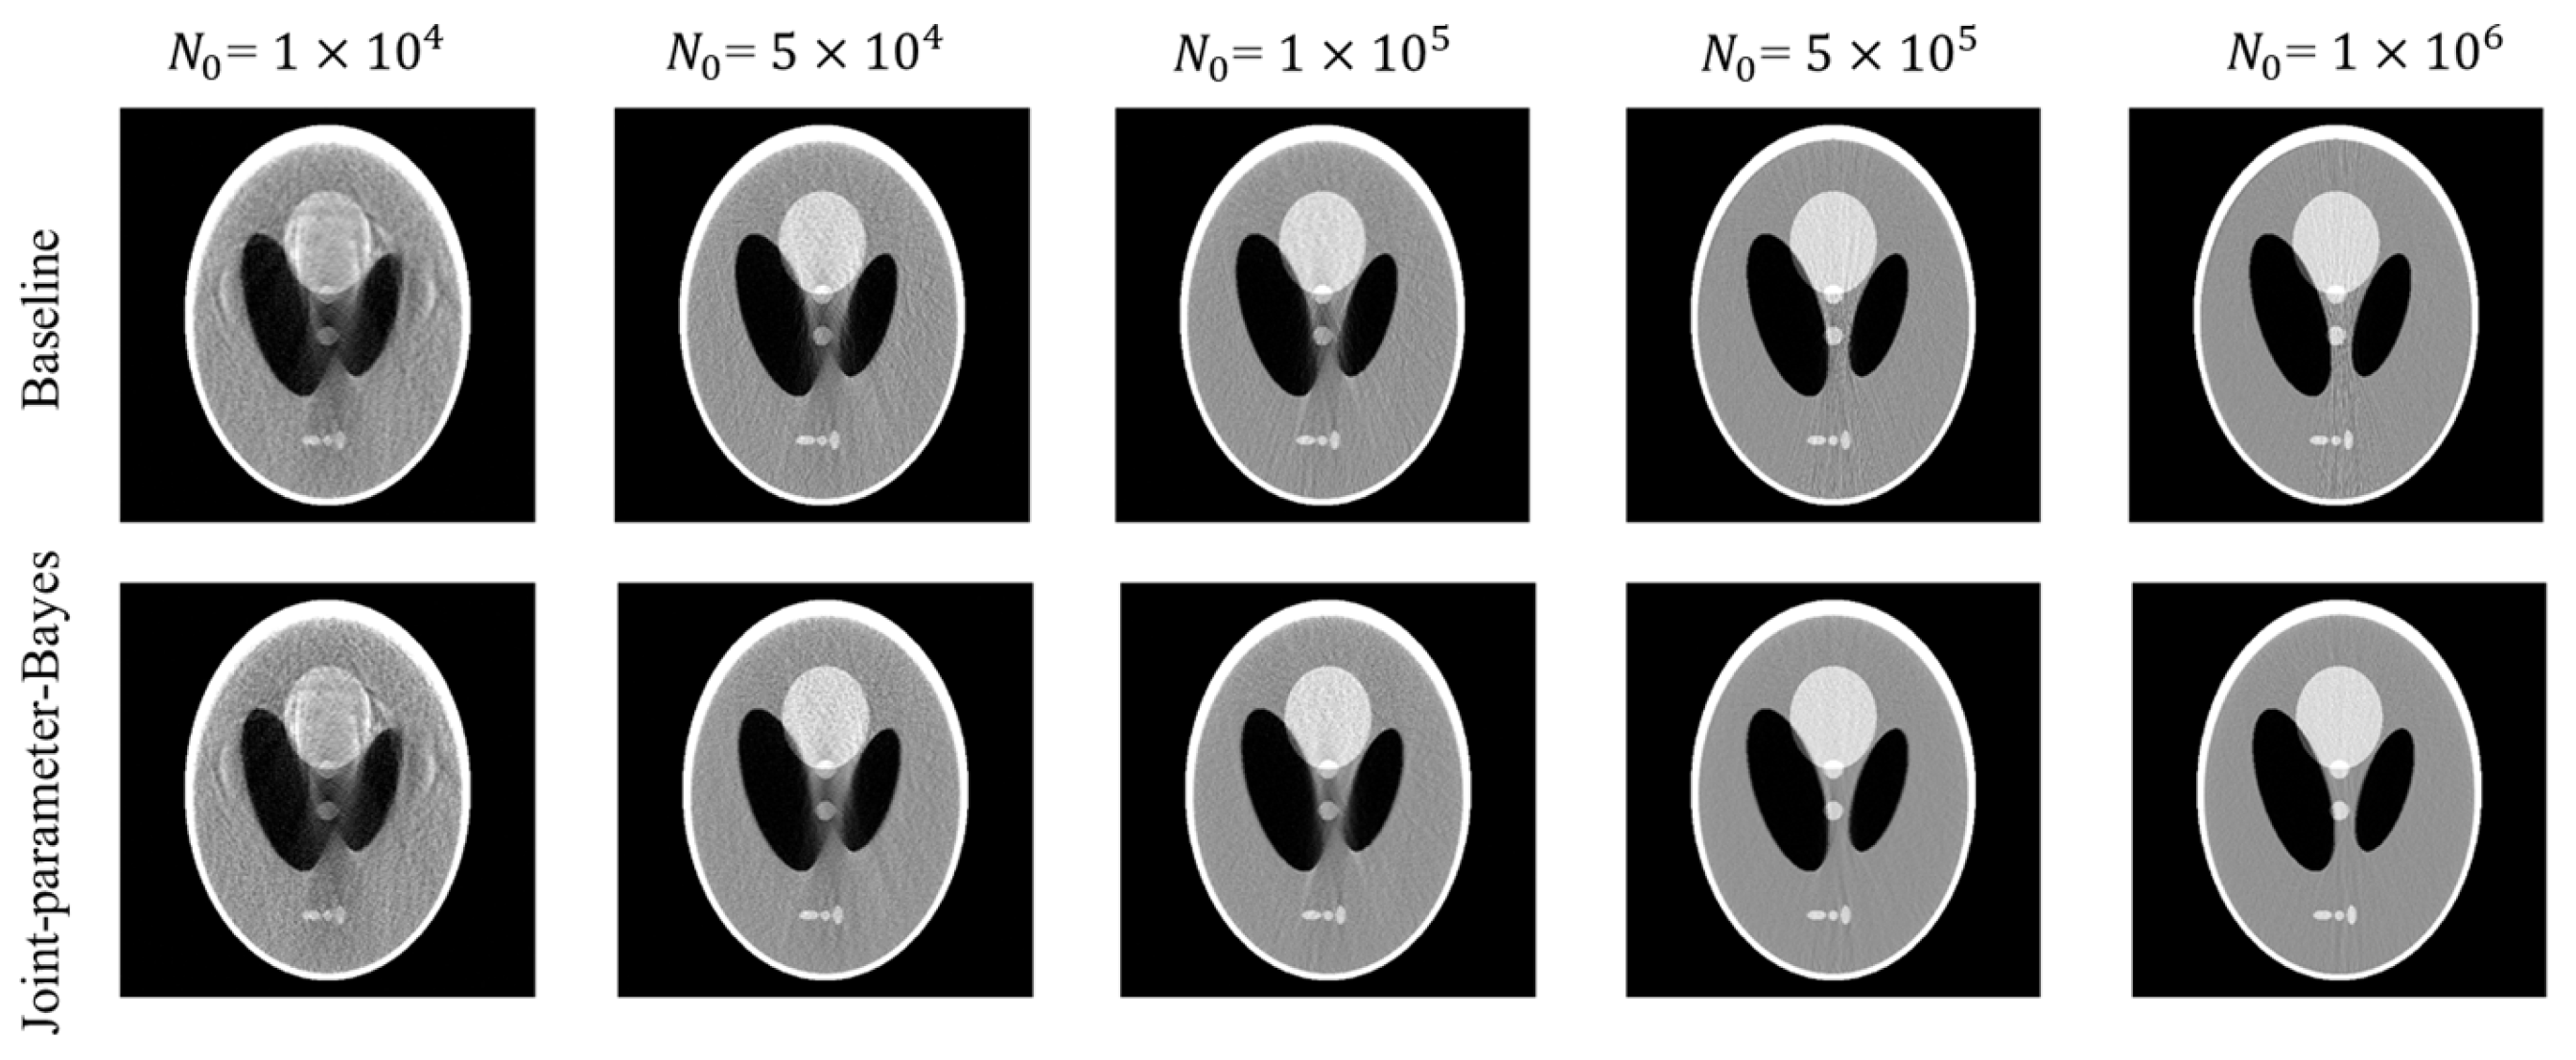

Figure A1 and Table A1 present the comparison results between the baseline and the proposed joint-parameter-Bayes on Poisson noise in post-log sinogram data. Figure A2 and Table A2 present the comparison results between the baseline and the proposed joint-parameter-Bayes on Poisson noise to pre-log transmission data.

Figure A2.

Comparison of reconstructed images between the conventional MAP (baseline) and joint-parameter-Bayes with Poisson noise to pre-log transmission data.